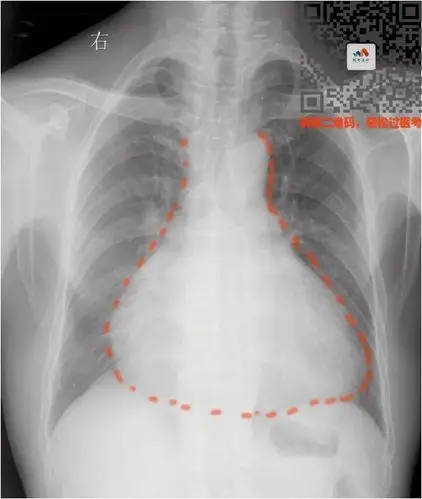

要么是心脏本身增大(心包积液—烧瓶心)要么是心包里面灌了水普大型